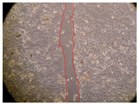

In the present study, the healing potential of 8 decoctions used in the preparation of ayahuasca was evaluated, using the wound scratch test. The evolution of the scratch created was monitored using microscopic images (Table 2) and the distance between the margins of the lesion was calculated (Table 3). Analysing the images that showed the evolution of the distance between the margins of the lesion and comparing them with the control samples, it was possible to verify that, in general, all the samples showed a great decrease in the lesion, and after 24 h of incubation, the samples of M. hostilis + P. harmala at 500 mg/L and P. viridis + B. caapi at 250 mg/L showed the best results. However, analysing the evolution of the distance calculated, only the sample of the commercial mixture at 250 mg/L after 2 h of incubation did not show a significant decrease. All other samples at different evaluation times, as well as the commercial mixture at 250 mg/L at the other times (8 h, 12 h and 24 h) showed a significant decrease in lesion margins compared to the control.

Table 2.

Microscopic images obtained from the scratch wound-healing assay with the samples of ayahuasca (magnification: 100×). The margins of the scratch appear in red.

These results are indicative of the healing activity of the samples tested. It is possible to observe in the images of Table 2 the migration of the fibroblasts incubated with the samples at different concentrations. In these images, it was possible to verify that the lesions closed over time, which was in accordance with the distance calculated between the margins of the lesion. As far as we know, to date there are no studies where the healing potential of ayahuasca has been evaluated, and it is not possible to compare the results now obtained. However, these results can be explained by the antioxidant and anti-inflammatory activity previously studied in these samples [], since it is reported that antioxidant activity and healing properties coexist in plant extracts []. Wound healing consists of the reconstruction of the lesion, involving several interactions between epithelial cells, growth factors, cytokines and chemokines. It has been reported that natural products, namely plant extracts, are involved in the proliferation of fibroblasts and keratinocytes, and may contain cell adhesion molecules, growth factors and cell signalling molecules, which can promote lesion reconstruction []. This in vitro assay, which, unlike conventional assays used to determine the healing properties of plant material, was non-invasive, allowed the screening of several samples with antibacterial, anti-inflammatory and antioxidant properties, which are important in wound healing [,].